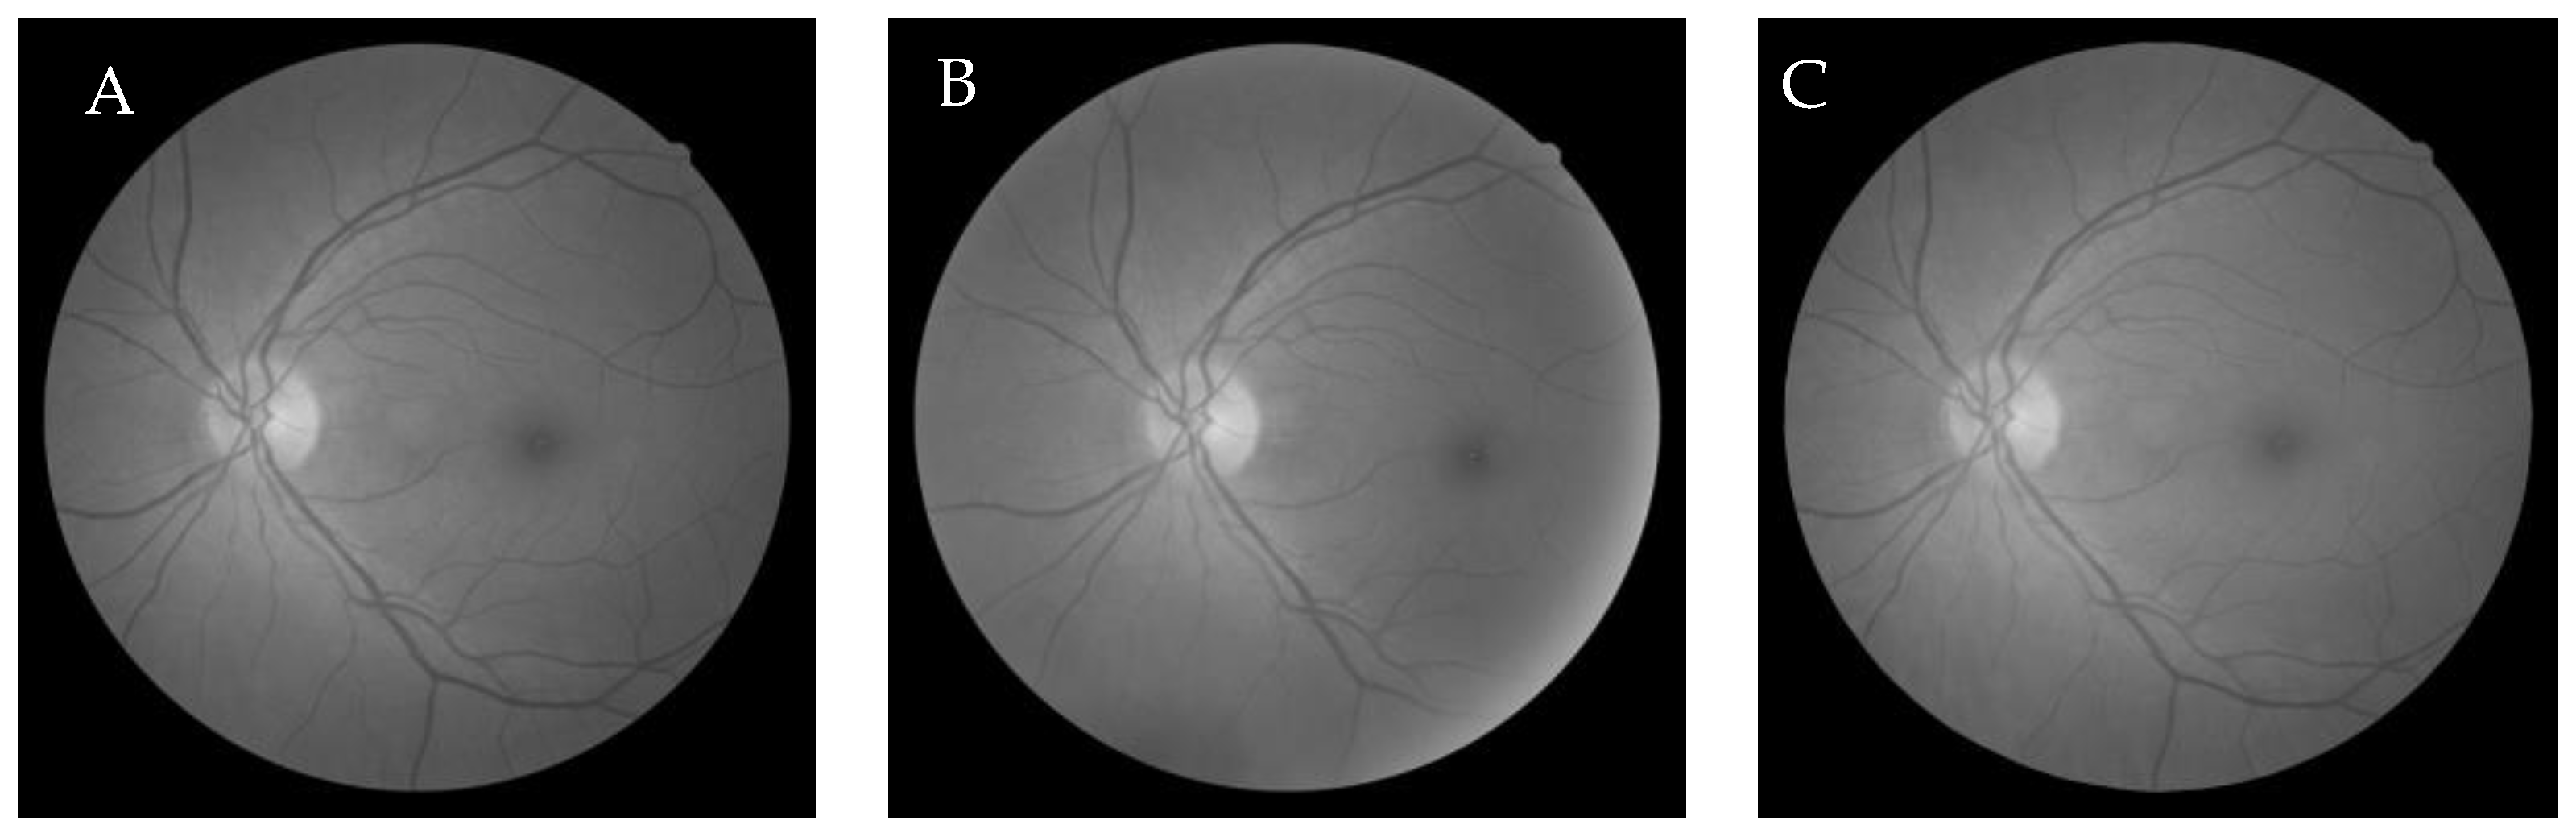

6.1. Dataset

6.2.2. Firefly Algorithm-Based Wang’s Demons Registration